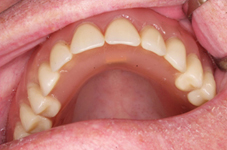

Bezzubá čelist je hlavní indikací pro ošetření pomocí implantátů. Zejména celkové zubní náhrady v dolní čelisti mají velice nízkou stabilitu a držení díky velkému úbytku kosti.

S pomocí zubních implantátů můžeme díky různým kotevním systémům (třmeny, kulové hlavy, Locatory) zajistit stabilitu a držení protézy nebo při použití většího počtu implantátů zhotovit pevné náhrady – můstky nalepené nebo našroubované na pevno na implantáty.

S těmito typy náhrad můžeme dosáhnout perfektní funkci, výbornou estetiku, fonetiku a současně zajistit u pacienta možnost dobré hygienickou péče a čištění, která je pro životnost implantátů velice důležitá.